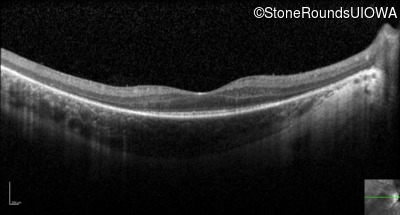

Optical Coherence Tomography - Left - 20/70

Exemplar / OCT Stack